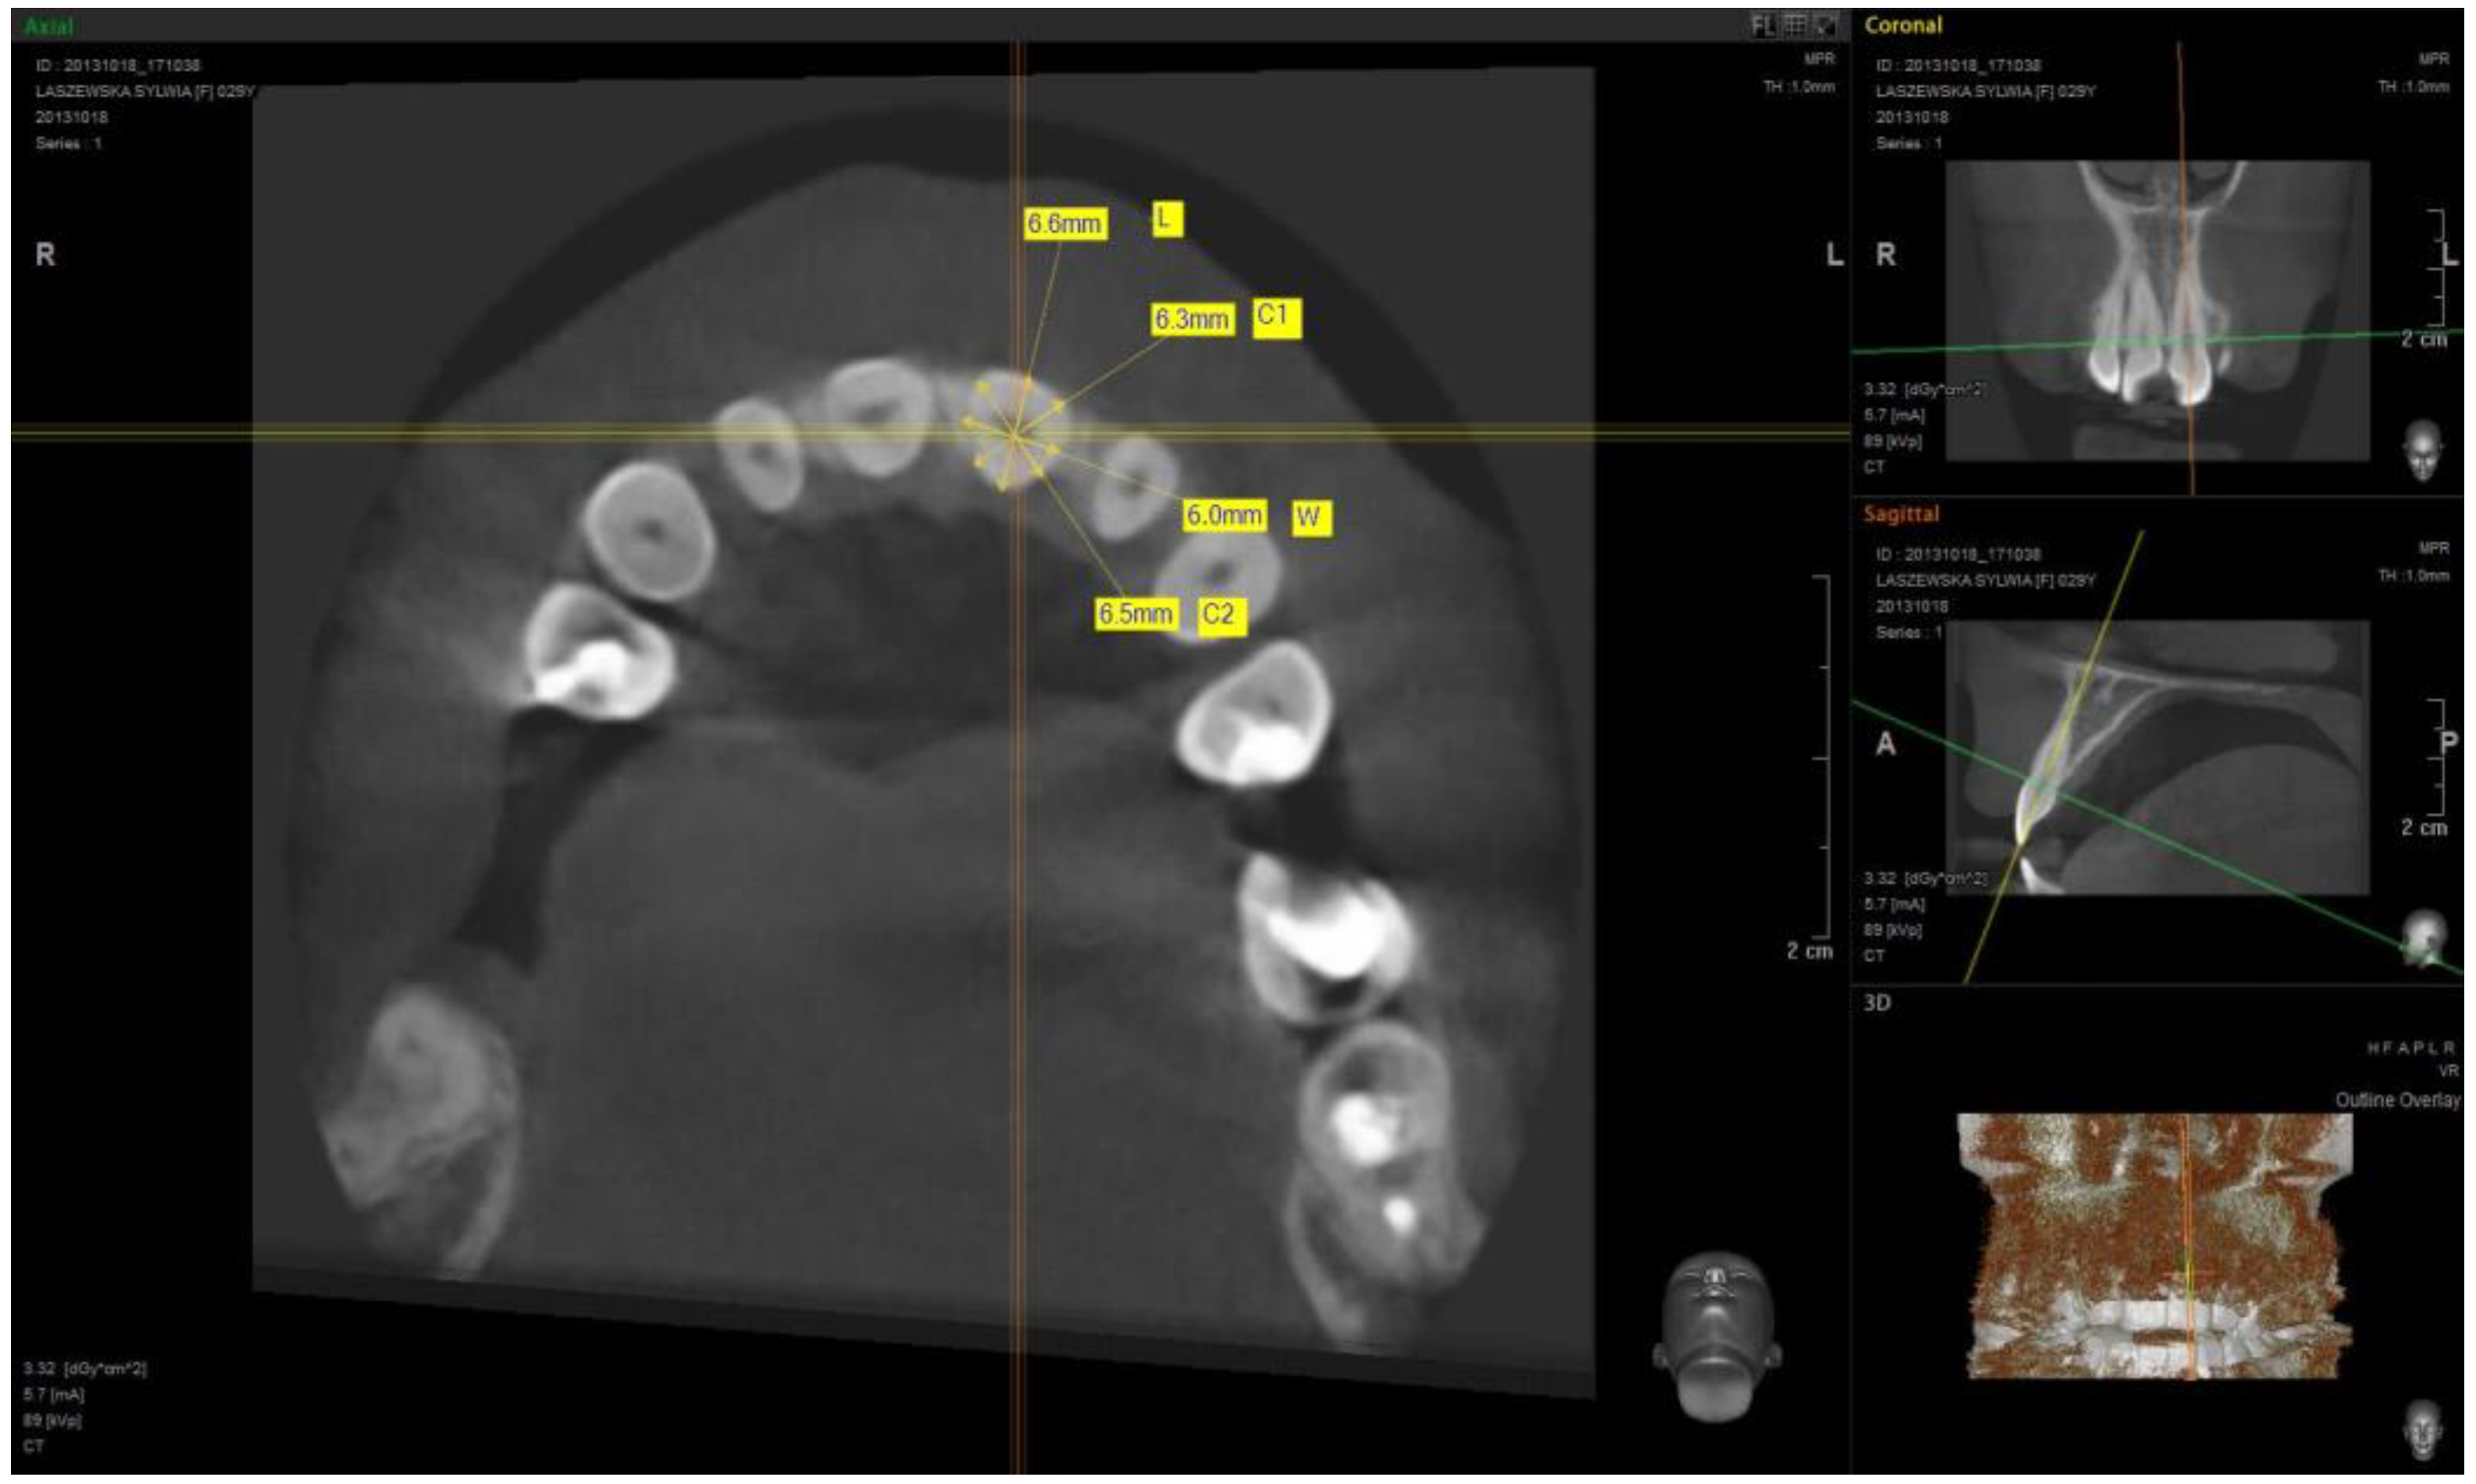

| L | C1 | H | C2 | L | C1 | H | C2 | L | C1 | H | C2 | L | C1 | H | C2 | L | C1 | H | C2 | |

| Arithemic Average | 6.633 | 6.302 | 5.889 | 6.787 | 6.085 | 5.65 | 4.447 | 5.533 | 7.693 | 7.023 | 5.358 | 6.536 | 8.509 | 7.611 | 4.569 | 6.957 | 10.320 | 9.963 | 7.577 | 10.084 |

| Standard Deviation | 0.546 | 0.478 | 0.600 | 0.538 | 0.525 | 0.545 | 0.579 | 0.506 | 0.578 | 0.599 | 0.532 | 0.679 | 0.619 | 0.634 | 0.602 | 0.704 | 0.751 | 1.023 | 0.696 | 1.159 |

| Median | 6.6 | 6.2 | 5.9 | 6.8 | 6.1 | 5.7 | 4.4 | 5.45 | 7.7 | 7 | 5.4 | 6.45 | 8.45 | 7.8 | 4.55 | 7 | 10.35 | 10.1 | 7.6 | 10.3 |

| Minimum Value | 5.8 | 5.5 | 4.5 | 5.5 | 5.1 | 4.4 | 3.4 | 4.5 | 6.4 | 5.9 | 4.5 | 5.2 | 7.2 | 6.2 | 3.1 | 5 | 8.1 | 7.3 | 6.4 | 7.1 |

| Maximum Value | 8 | 7.5 | 7.7 | 8.6 | 7.4 | 7 | 6.4 | 6.9 | 8.9 | 8.6 | 6.6 | 8.2 | 9.8 | 8.7 | 5.8 | 8.3 | 11.8 | 11.9 | 9 | 12.4 |